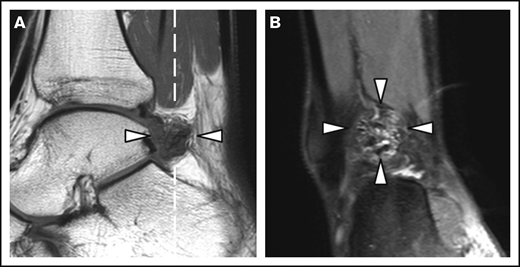

MRI of a right ankle with synovial hypertrophy and hemosiderin deposits. Synovial hypertrophy and hemosiderin deposits (arrowheads) on a sagittal T1-weighted MRI (A) and the coronal proton density–weighted MRI with fat suppression (B). The dashed white line in panel A represents the imaging plane of panel B.

Patient and joint characteristics are presented in Table 1. At baseline, patients were aged 12 to 29 years. Prophylaxis was given in 15 (94%) of 16 patients with severe hemophilia (weekly dose, 38 IU/kg; IQR, 23-44 IU/kg) and in 1 (13%) of 8 patients with moderate hemophilia. Details on treatment and adherence have been published previously.11 Treatment remained unchanged during follow-up. None of the patients was treated for clinical synovitis at baseline. Clinical function was good according to the Hemophilia Joint Health Score (HJHS) assessed within 2 years of MRI (median HJHS, 0; IQR, 0-1). The majority of joints (82%) had a history of bleeding before MRI (median lifetime number of joint bleeds/joint, 2; IQR, 1-5). At baseline, the AJBRs for knees and ankles combined were low (median, 0.2; IQR, 0.5-1.2). Although radiographic abnormalities were observed in 7% of joints only, 39% of joints showed MRI abnormalities, including 24 of 48 ankles and 15 of 52 knees. The most prevalent MRI findings were effusion (23%), synovial hypertrophy (16%), and hemosiderin deposits (16%). Synovial hypertrophy and hemosiderin deposits were mostly concurrent findings; 14 of 16 joints (87.5%; confidence interval [CI], 61.7-98.5) with synovial hypertrophy showed hemosiderin deposits, and 14 of 16 joints (87.5%; CI, 61.7-98.5) with hemosiderin deposits showed synovial hypertrophy. Ankles exhibited synovial hypertrophy and hemosiderin deposits significantly more often than knees (P < .01). Figure 1 presents an example of concomitant findings of synovial hypertrophy and hemosiderin deposits in an ankle. There were no significant differences in the baseline joint characteristics between patients with moderate hemophilia treated on demand and patients with severe hemophilia on prophylaxis, nor in bleeding rates during follow-up.